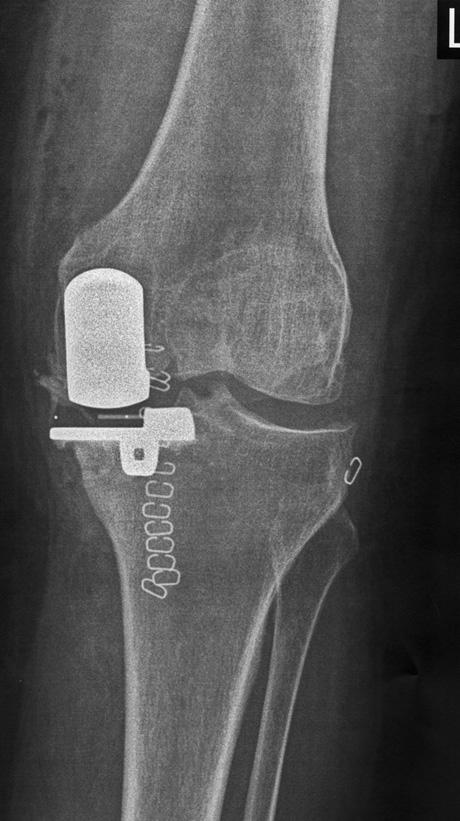

Ακτινολογική εικόνα της μονοδιαμερισματικής αρθροπλαστικής. Το υγιές τμήμα της άρθρωσης παραμένει ανέπαφο.

Μονοδιαμερισματική αρθροπλαστική Oxford Zimmer Biomet για την αντικατάσταση του έσω διαμερισματος της άρθρωσης του γόνατος το οποίο πάσχει από οστεοαρθρίτιδα.